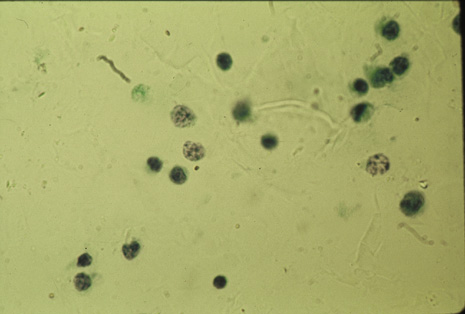

Many forms of uveitis are characterized by specific types of inflammatory cells. Usually, however, one encounters mixtures of cell types in any given specimen, with the relative percentages of lymphocytes and polymorphonuclear leukocytes varying. There may be unusual numbers of eosinophils, or macrophages laden with lens material may be present. Thus, an enumeration of the cells and a careful analysis of their structure can be useful as a diagnostic aid (Figs. 7, 8, 9, 10, 11, 12, 13, 14, 15, 16, 17, 18, 19, and 20). Figure 15 demonstrates eosinophils that were aspirated from the anterior chamber of a patient with Toxocara canis endophthalmitis. Figure 12 demonstrates malignant cell infiltrate from the vitreous, showing the stained presence of monoclonal light chains being elaborated in the cytoplasm. Interleukin-10, detectable in the vitreous of intraocular lymphoma patients, is also directly indicative of both the clinical activity and the number of malignant cells as observed by cytopathology.

Precise identification and culture of bacterial and fungal pathogens from both the aqueous humor and the vitreous fluid can be obtained. Gram's stain and Giemsa's stain smears of centrifuged specimens from the aqueous humor and the vitreous humor frequently demonstrate the bacterial or fungal causative agent. Attempts to isolate bacteria and fungi and to identify them on Gram's stain or Giemsa's stain smears have been most rewarding in the following cases: (a) postoperative endophthalmitis, (b) infection after a penetrating injury of the eye, (c) drug abuse patients with endogenous endophthalmitis (Figs. 21, 22, 23, 24, and 25), (d) patients receiving hyperalimentation, and (4) patients who are immunocompromised as a result of exogenous immunosuppressive agents.